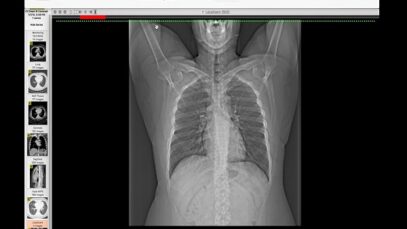

How I Read a Chest CT

What are some common uses of the procedure? Doctors use chest CT to: examine abnormalities found on chest x-rays. help diagnose the causes of signs or symptoms of chest disease, such as cough, shortness of breath, chest pain, or fever. detect and evaluate the extent of tumors that arise in the chest, or tumors that […]